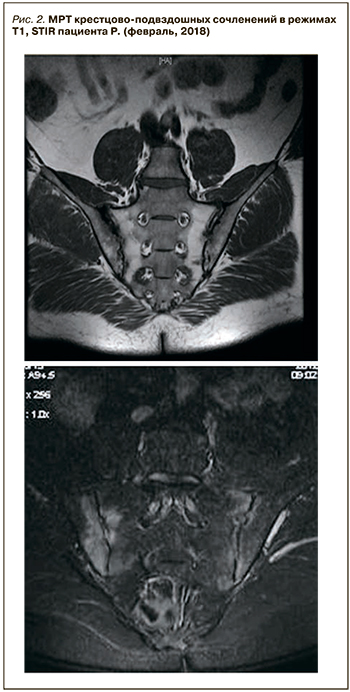

В феврале 2018 г. на фоне стрессовой ситуации пациент обратился с обострением псориаза волосистой части головы (с выраженным шелушением и покраснением), суставного синдрома (припухлость и боль в голеностопных суставах – 60 мм по визуально-аналоговой шкале), а также с впервые появившейся выраженной болью во всех отделах позвоночника (70 мм по визуально-аналоговой шкале), чаще возникавшей ночью и в периоды покоя и облегчавшуюся после движения, с длительной утренней скованностью. Данные лабораторных исследований: резкое повышение СРБ (32 мг/л), ASDASCRP=3,6. Ввиду появления характерной симптоматики и высокого риска прогрессирования назначено дообследование (МРТ и рентгенография крестцово-подвздошных сочленений). По результатам МРТ крестцово-подвздошных сочленений в режимах T1, STIR обнаружены признаки острого (двусторонний остеит крестцово-подвздошных сочленений) и хронического («бэкфил», эрозии) воспаления (рис.2), по данным рентгенографии крестцово-подвздошных сочленений – признаки двустороннего сакроилеита 2 стадии (рис. 3).

В феврале 2018 г. на фоне стрессовой ситуации пациент обратился с обострением псориаза волосистой части головы (с выраженным шелушением и покраснением), суставного синдрома (припухлость и боль в голеностопных суставах – 60 мм по визуально-аналоговой шкале), а также с впервые появившейся выраженной болью во всех отделах позвоночника (70 мм по визуально-аналоговой шкале), чаще возникавшей ночью и в периоды покоя и облегчавшуюся после движения, с длительной утренней скованностью. Данные лабораторных исследований: резкое повышение СРБ (32 мг/л), ASDASCRP=3,6. Ввиду появления характерной симптоматики и высокого риска прогрессирования назначено дообследование (МРТ и рентгенография крестцово-подвздошных сочленений). По результатам МРТ крестцово-подвздошных сочленений в режимах T1, STIR обнаружены признаки острого (двусторонний остеит крестцово-подвздошных сочленений) и хронического («бэкфил», эрозии) воспаления (рис.2), по данным рентгенографии крестцово-подвздошных сочленений – признаки двустороннего сакроилеита 2 стадии (рис. 3).

Вследствие присоединения новых клинических симптомов в виде воспалительной боли в спине, патогномоничных признаков на рентгенографии и МРТ крестцово-подвздошных сочленений проведена ревизия прежнего диагноза и выставлен новый: «АС, очень высокой активности, HLA-B27+, Ro-стадия сакроилеита 2, МРТ-остеит, артрит, энтезит, дактилит в анамнезе, псориаз волосистой части головы».

Особенностью данного клинического случая является дебют заболевания с периферического артрита, наличие у пациента псориаза, энтезита, дактилита в анамнезе, в результате чего был диагностирован ПсА и назначен метотрексат как препарат выбора в терапии артрита и псориаза. В связи с изменением клинической картины (появление воспалительной боли в спине), а также с учетом ранее выявленного HLA-B27 и появления изменений по результатам МРТ и рентгенографии крестцово-подвздошных сочленений (признаки острого и хронического воспаления) в короткие сроки диагноз ПсА был пересмотрен и выставлен АС.